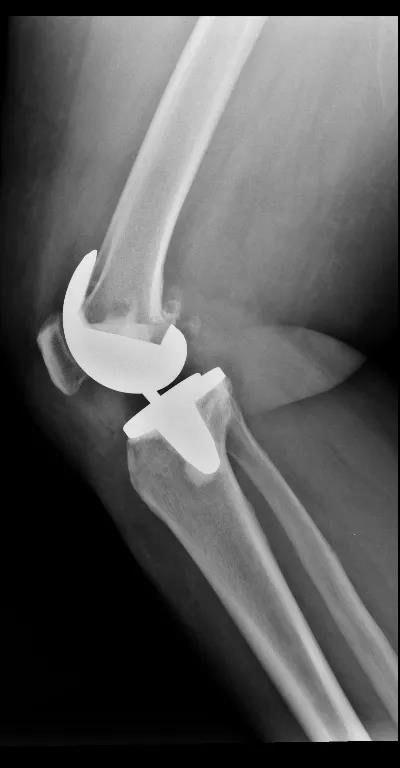

因施女士有冠心病支架植入病史,术前通过心内科、麻醉科多学科会诊后,决定一期行右全膝关节置换术,二期再行左侧膝关节置换手术治疗。8月4日,在张金山副院长的带领下,为施女士顺利地进行了右侧人工全膝关节置换术,手术效果十分显著。